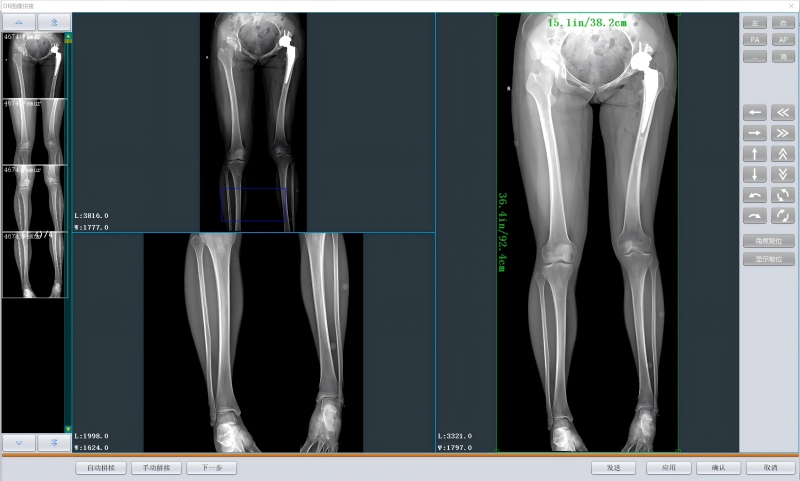

星灵DR长骨拼接工作站针对放射科下行脊柱及下肢、下肢静脉造影等分段摄片检查图像,进行全长图像拼接,所得图像清晰、连续完整、无色差,弥补了受各种影像学检查范围的局限性,为骨科临床医师重构出人体骨骼的全景图像,完全满足临床需求,拼接过程支持全自动和手动拼接两种方式。

拼接.jpg